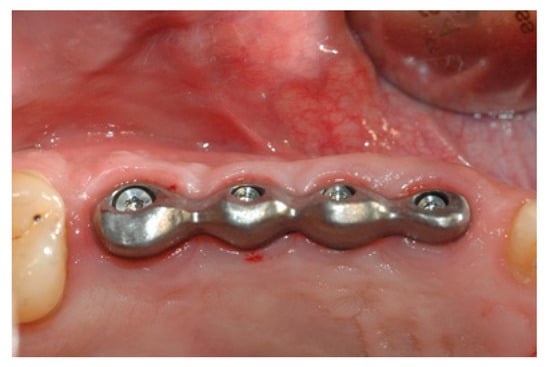

Six months after the insertion of the implants, an operation was performed to uncover the implants and mount the healing abutments. A few weeks later, the impression was taken by means of an individual tray with the pick-up technique (Figure 5 and Figure 6).

Figure 5. Impression and structure made.

Prosthesis 02 00023 g005

Figure 6. Impression and structure made.

Prosthesis 02 00023 g006